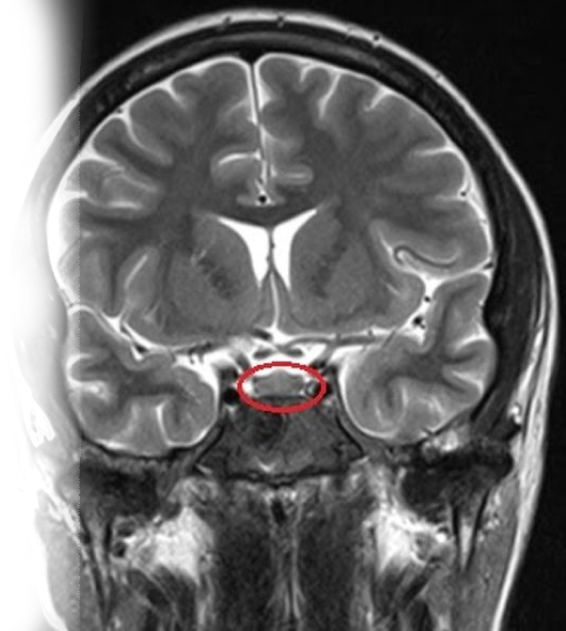

Магнитно-резонансная томография гипофиза с контрастированием – важный метод исследования с введением контрастного вещества, который позволяет визуализировать гипофиз, частично — структуры головного мозга.